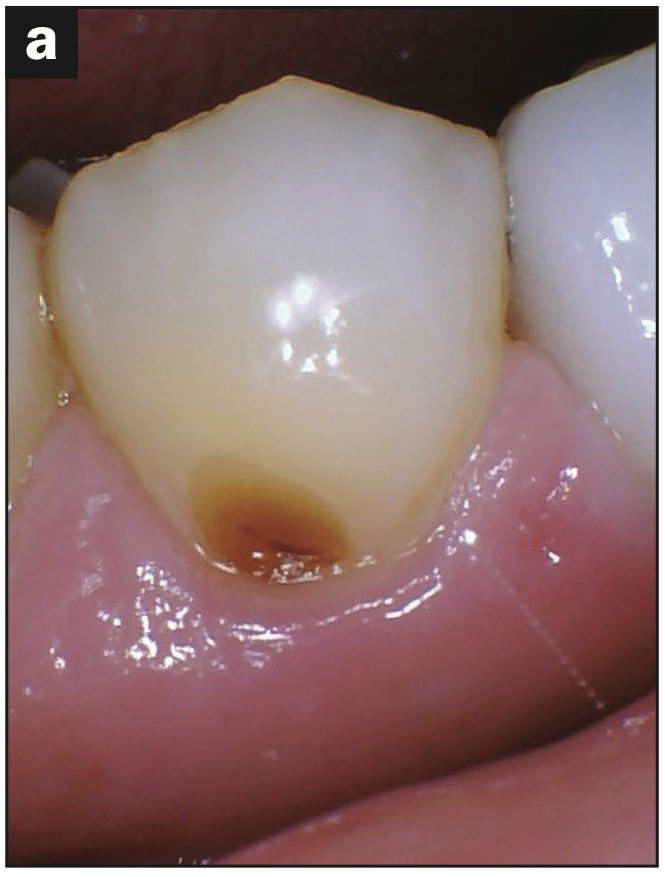

Intraoral images were captured, focusing on three surfaces of each tooth: buccal, occlusal/incisal, and lingual surfaces. The following issues were identified:

- Occlusal pitting (Figure 3a)

- Occlusal wear (Figures 3b and 3c)

- Decay (Figures 3b and 3d)